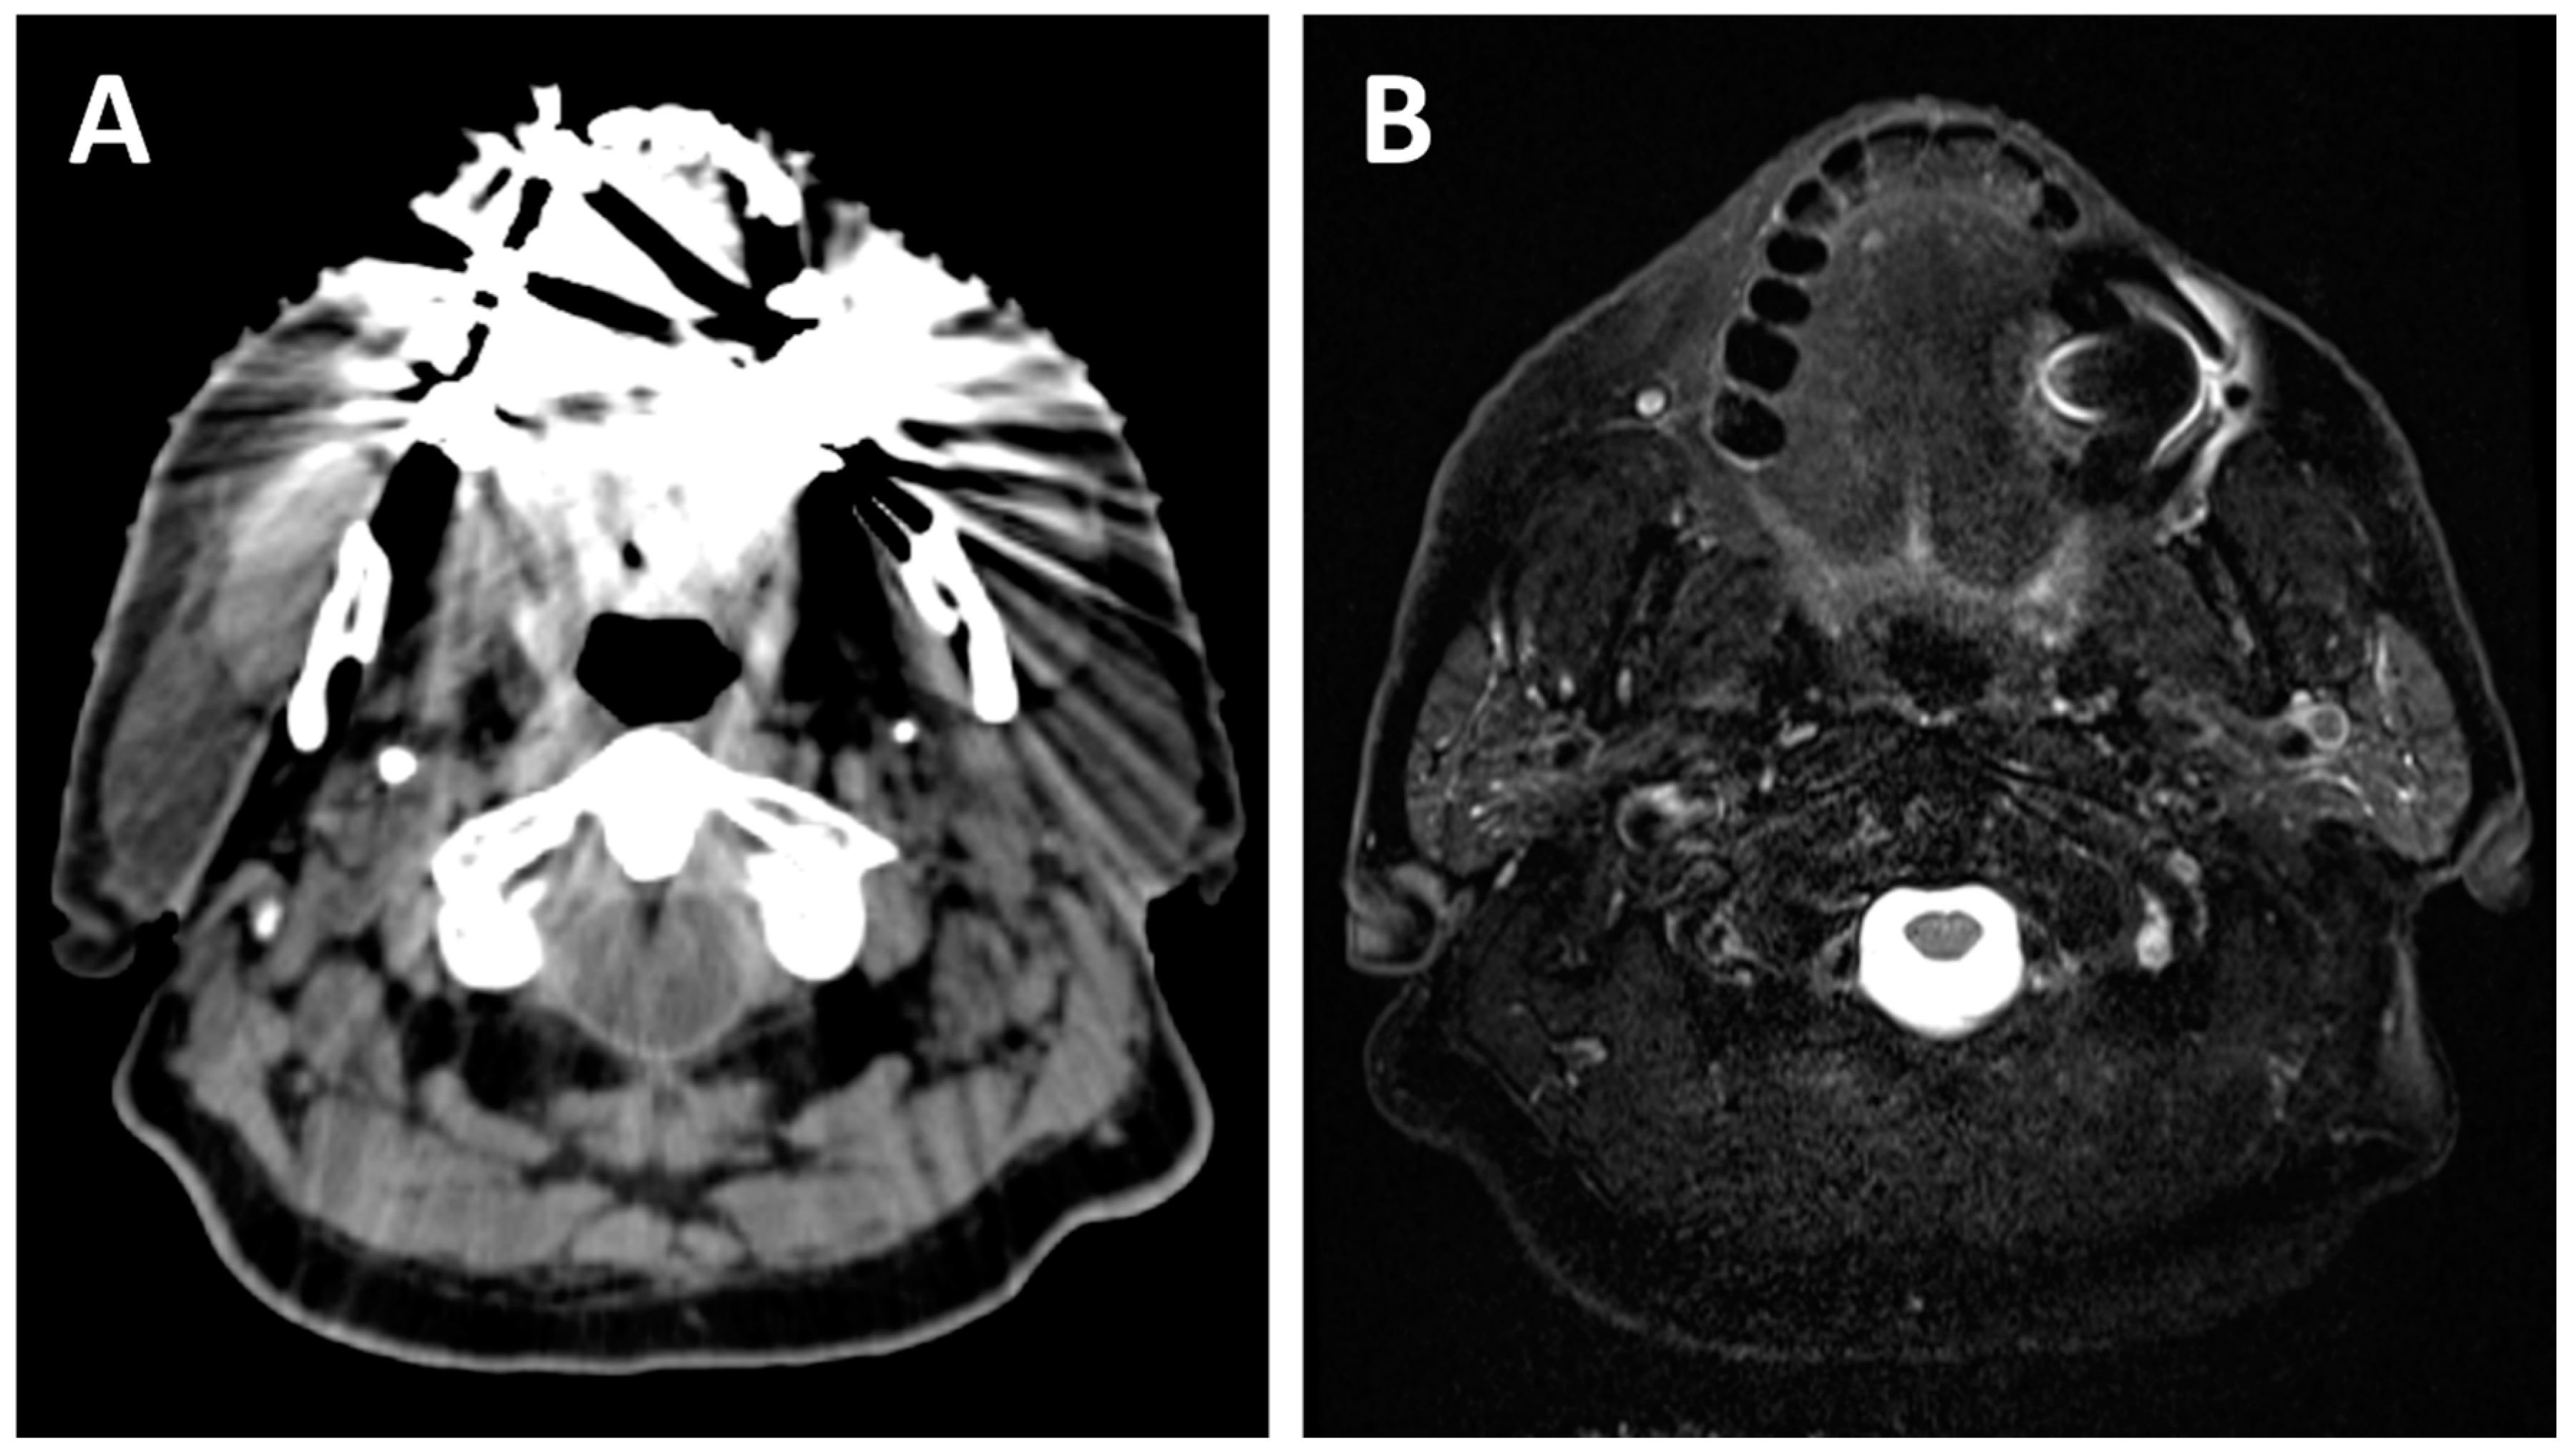

2.1. Local Extension

2.2. Lymph Node Evaluation